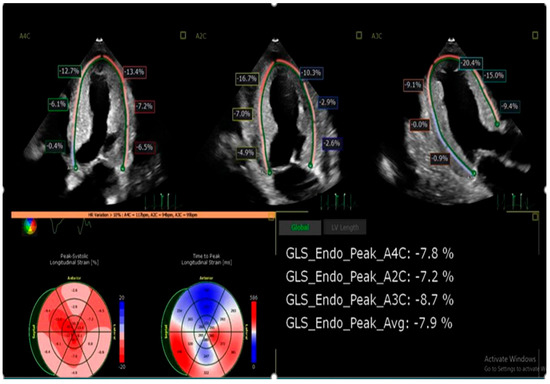

Multimodality Imaging in Cardiac Amyloidosis

by Mayuresh Chaudhari and Mahi Lakshmi Ashwath

Cardiac amyloidosis is an underdiagnosed cause of heart failure characterized by extracellular deposition of misfolded proteins. Advances in non-invasive imaging, including echocardiography, cardiac magnetic resonance imaging (CMR), and radionuclide imaging, have significantly enhanced the diagnostic accuracy and monitoring of cardiac amyloidosis. This review [...] Read more.

Cardiac amyloidosis is an underdiagnosed cause of heart failure characterized by extracellular deposition of misfolded proteins. Advances in non-invasive imaging, including echocardiography, cardiac magnetic resonance imaging (CMR), and radionuclide imaging, have significantly enhanced the diagnostic accuracy and monitoring of cardiac amyloidosis. This review explores the role of each modality, their individual strengths, and current consensus recommendations. Emphasis is placed on the integration of multimodal imaging to guide diagnosis, prognosis, and therapeutic decisions in both AL and ATTR amyloidosis. Full article

Show Figures

Figure 1